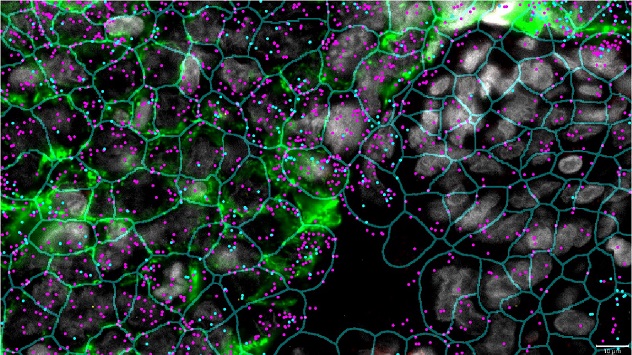

Spatial biology is an emerging and innovative field of biological research that focuses on the spatial arrangement and interactions of cells, molecules, and tissues within their native biological environments. By preserving the physical context of biological samples, spatial biology allows researchers to pinpoint the precise locations where specific genes, proteins, and other biomolecules are expressed within tissues. Advanced techniques, such as spatial transcriptomics, multiplexed imaging, and mass spectrometry imaging, have enabled the high-resolution mapping of molecular activities. This approach is revolutionizing our understanding of complex biological processes, including tumor microenvironments, immune responses, and neural networks, and is making significant contributions to drug discovery, diagnostics, and personalized medicine.